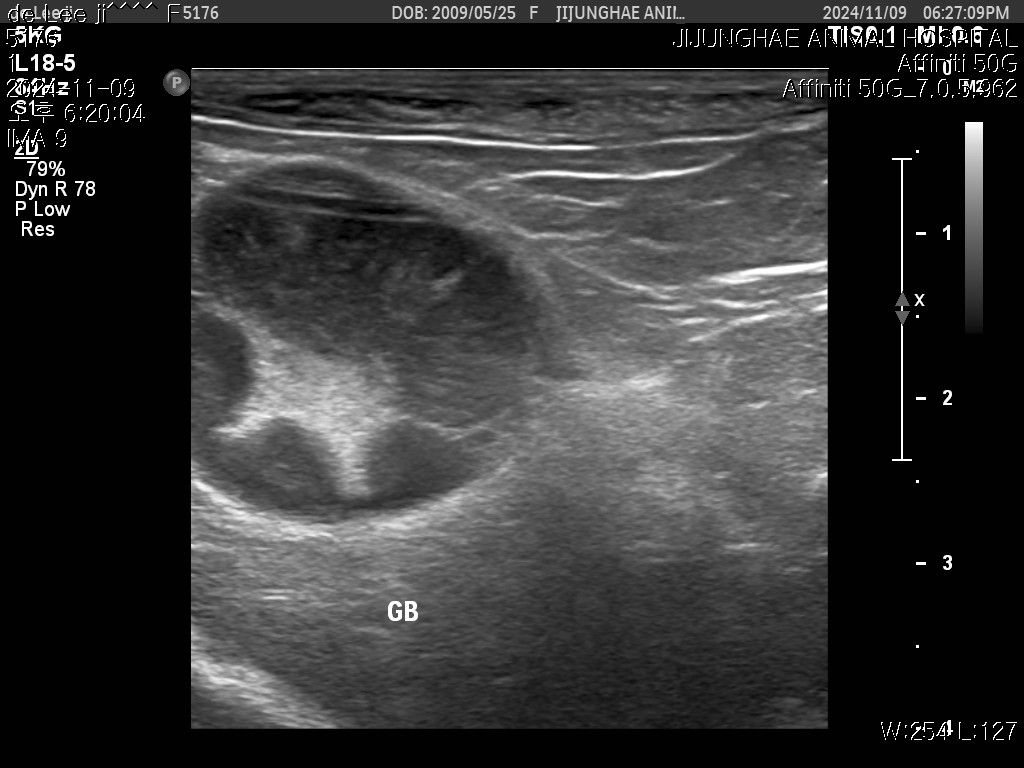

다만문제는 담낭점액종이 있다고 하시더라구요

작년 검진때도 듣긴했는데 올해 다시 초음파를보니

키위모양으로 있던데..찾아보니 키위모양이 많이위험하다고들었습니다

초음파사진 같이첨부하니 아이의 점액종 상태가

어떤지좀 봐주세요 제발부탁드립니다 !!!🙏